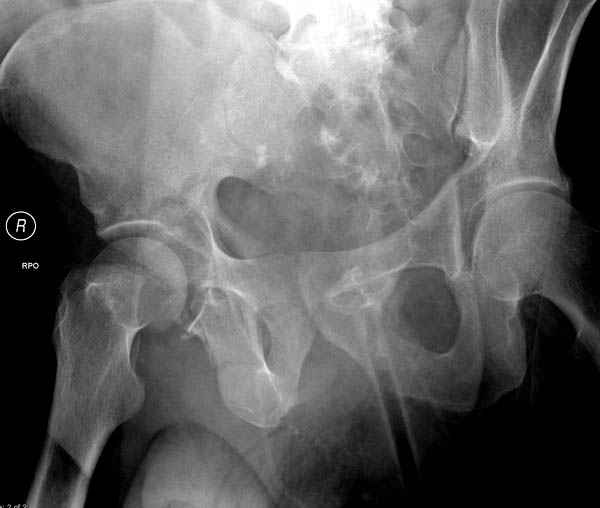

Прооперирован вчера на 13 день после поступления.

Больному 41 и из-за гемодинамической нестабильности в течение первых 7 дней был в реанимации под интубационной седацией.

Кроме перелома плеча у больного старый дистракционный перелом T12-L1 оперированный когда-то и кем-то, открытый перелом костей предплечья, который был прооперирован в ночь поступления, после I&D (хирургической обработки). Из-за разрыва селезенки при поступлении травма хирургами произведено удаление.

Дополнительно имеется перелом ацетабулума: задняя

колонна с полупоперечным переломом, и переломы костей лица.

На седьмой день зафиксирован перелом ацетабулума через задний доступ. Перед операцией для профилактики DVT, IVC фильтер, также получает Lovenox.

Извиняюсь за качества снимков, обычный больной в 300 фунтов, портативным ренген аппаратом не пробить.

Очень хорошаая работа, поздравляю! Хотелось бы увидеть снимок таза до операции. Каким образом и как долго предполагаете разгружать тазобедреннй сустав в дальнейшшем?

Отправитель: Evgueny Tchekashkine 30 Ноябрь 2007, 16:57

По возможности вышлите снимки, сканы таза до реконструкции, интраоперационные.

По снимку создается впечатление о высоком поперечном переломе, задней колонны, стенки; почему не пользовались *magic screw*?